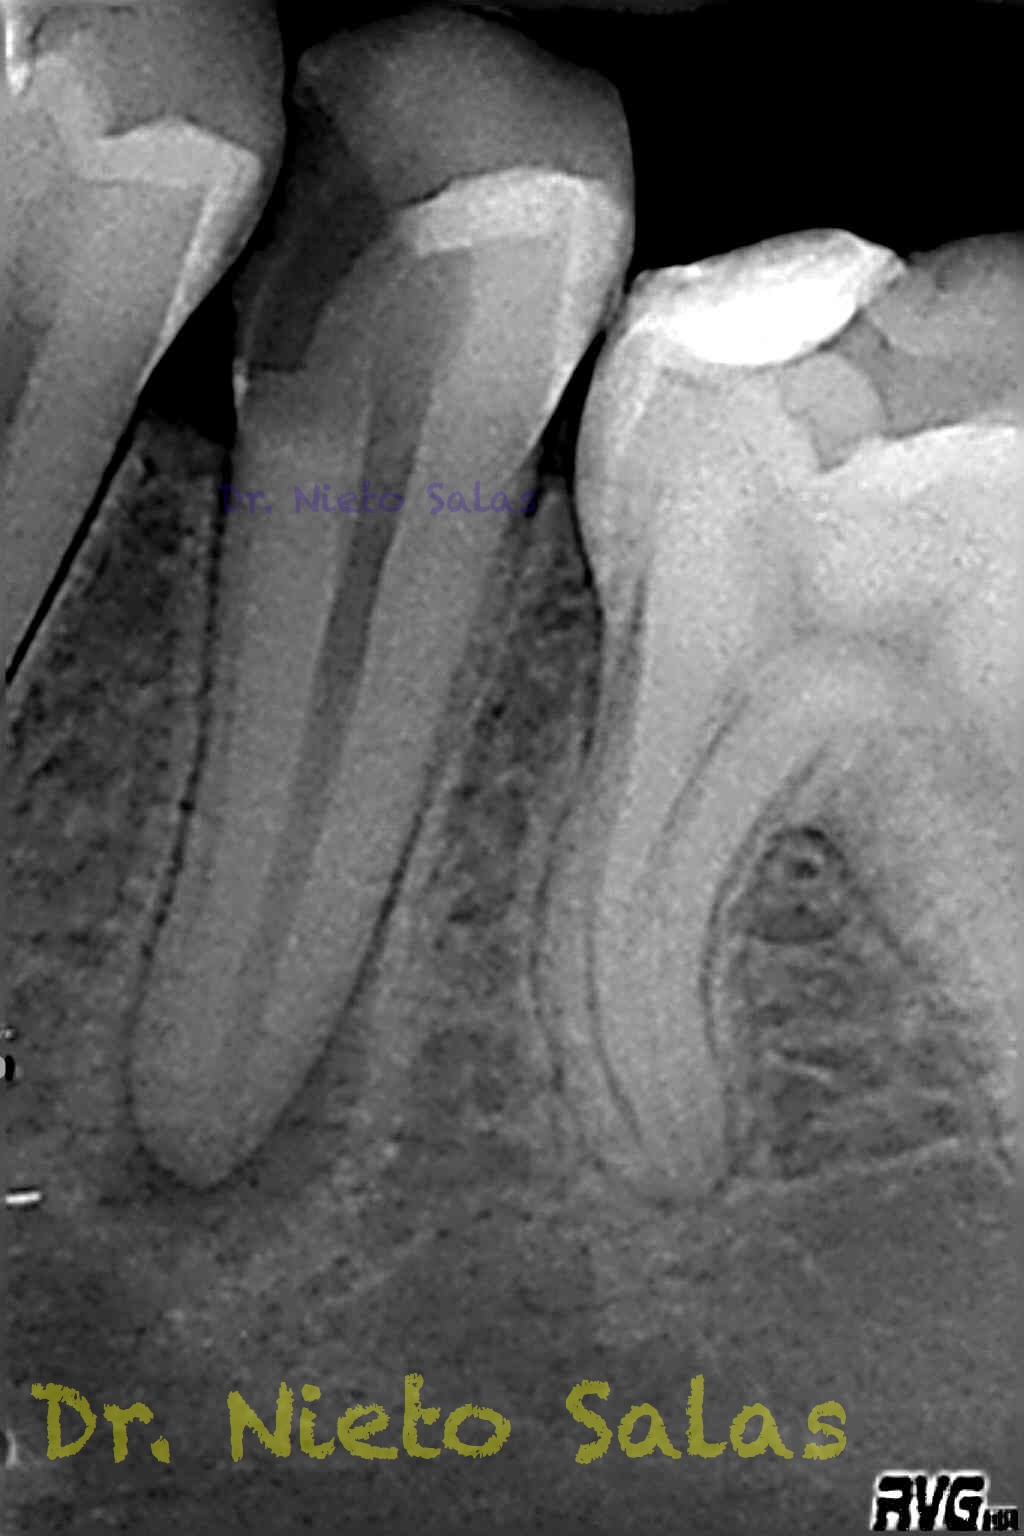

Nos llega a la clínica  este 4.5 con necrosis y periodontitis apical. la instrumentación se realizó con técnica de crown-down con limas K3 (SybronEndo) y la obturación con la técnica de ola continua de Buchanan, el tiempo de trabajo (para mi bastante importante) sobre 70-90 min.